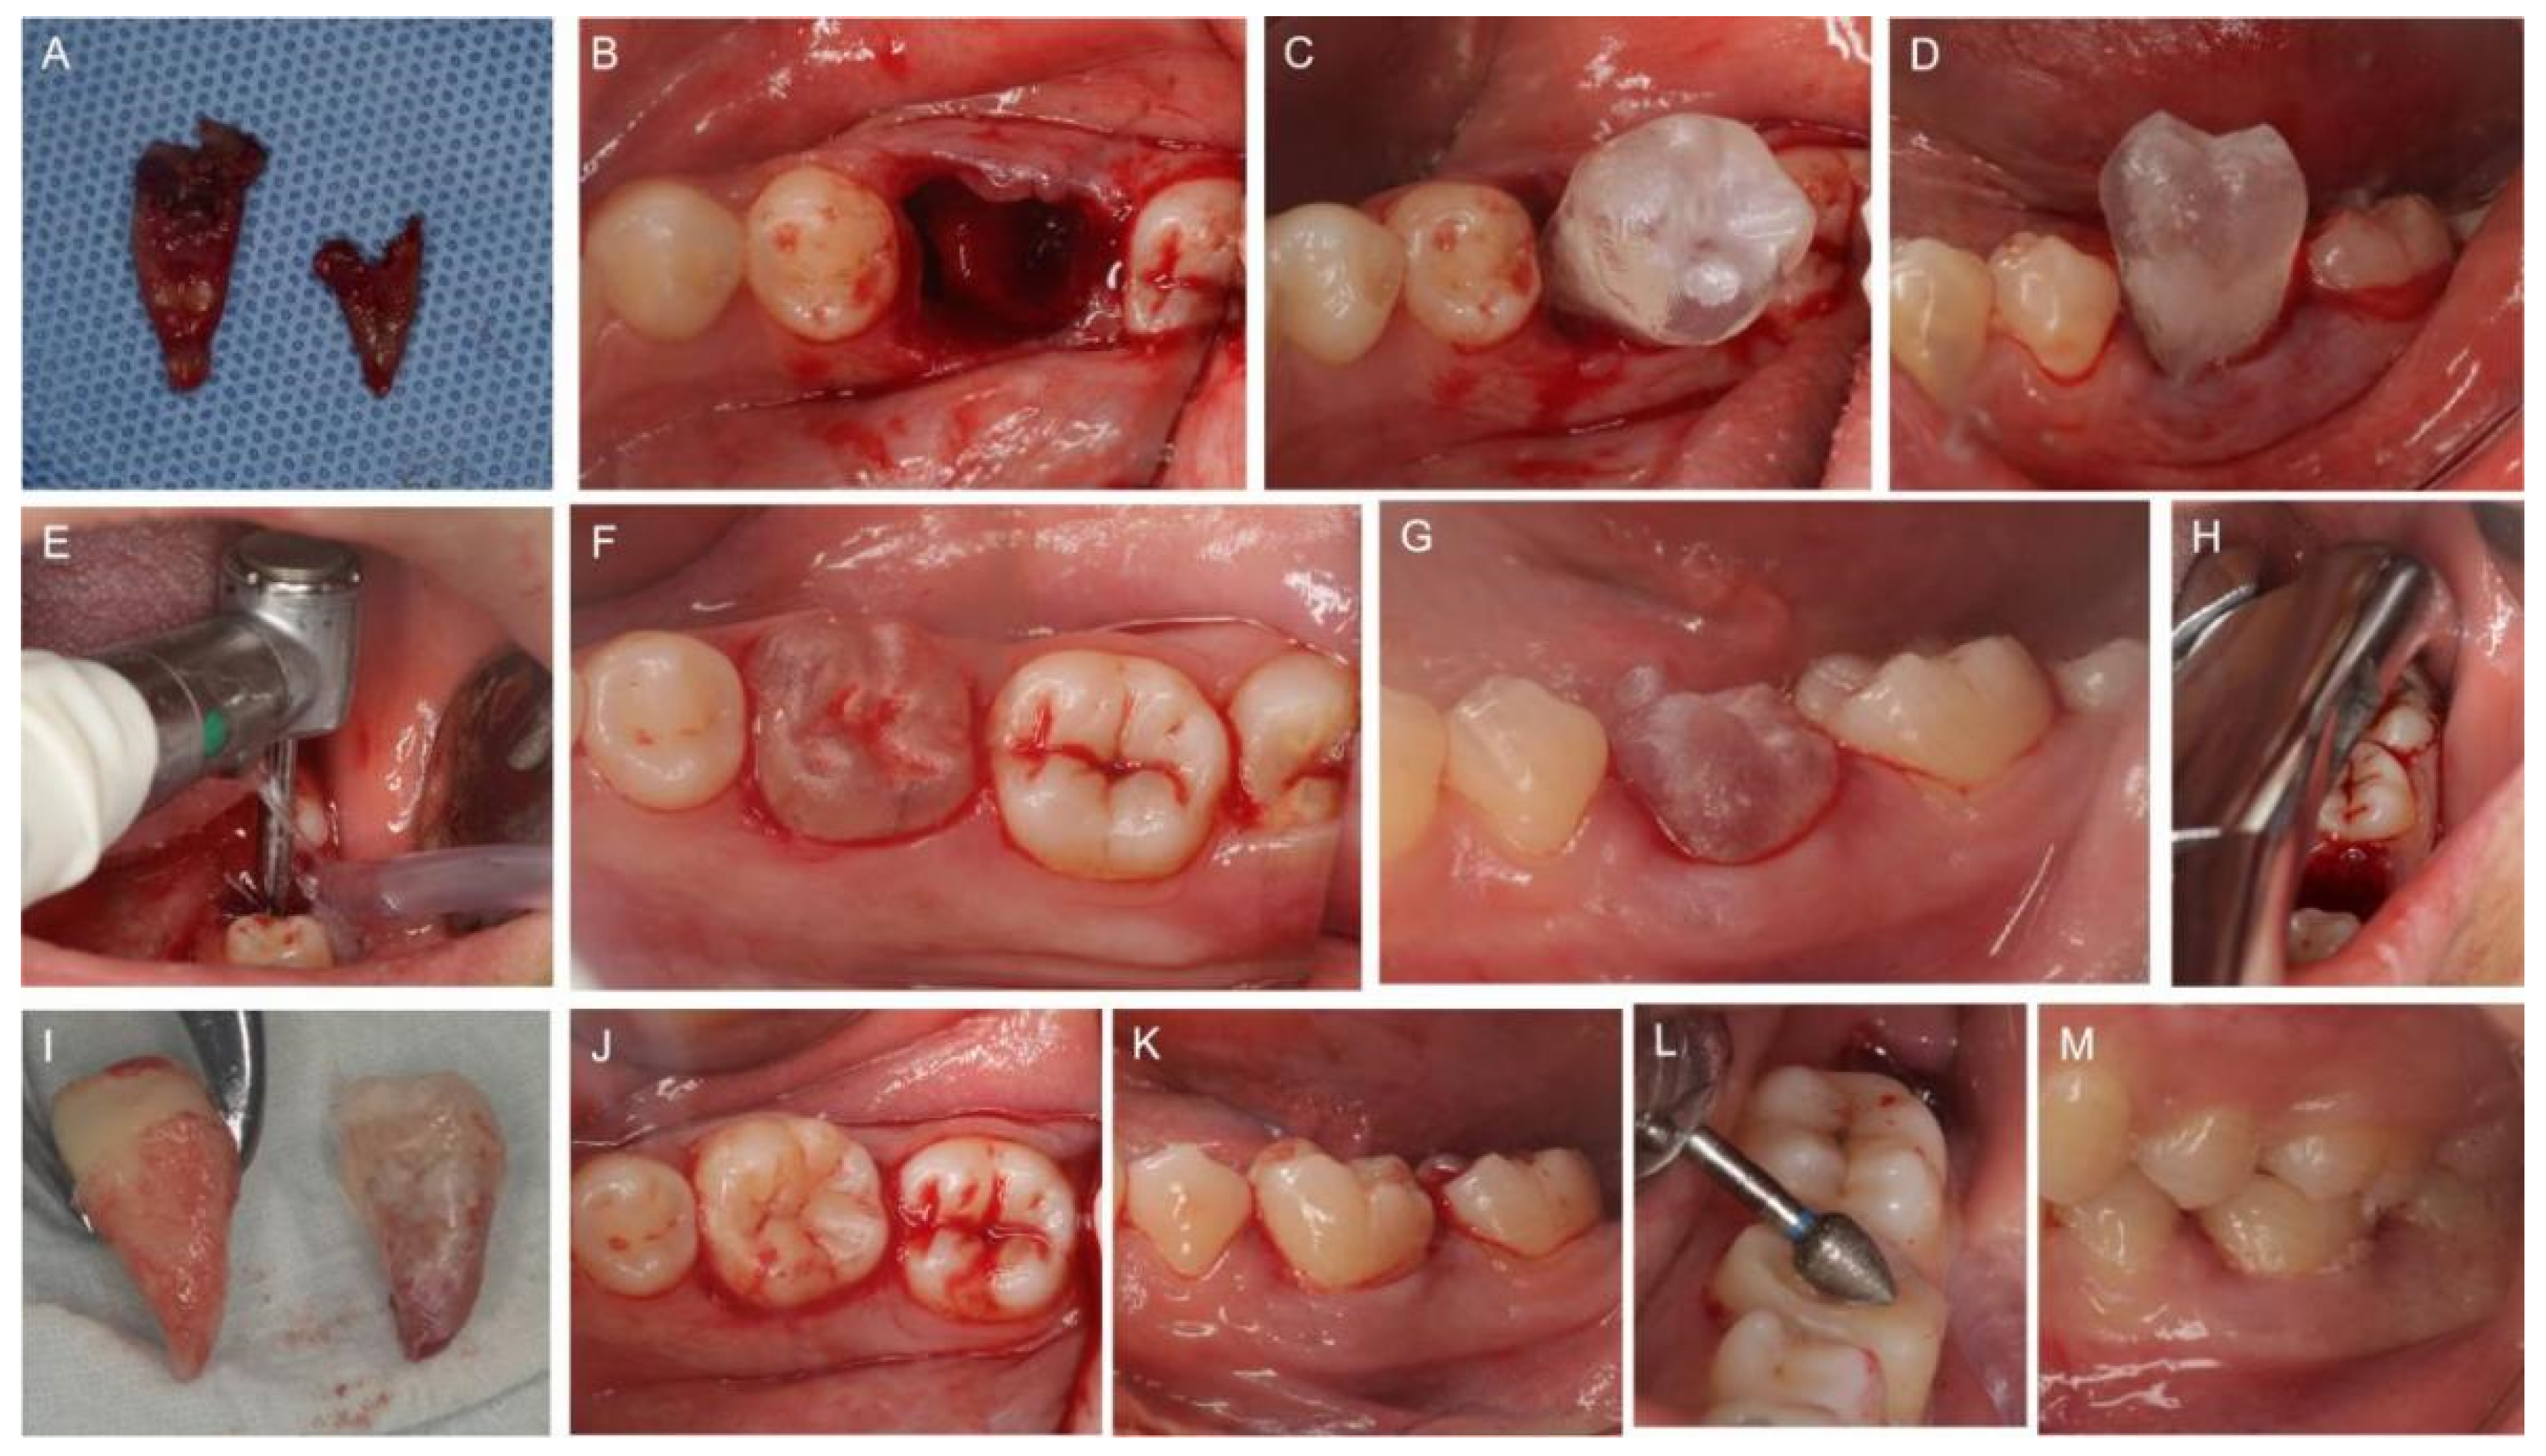

2.2. Preoperative Virtual Simulation and Fabrication of the CARP Models

2.3. Clinical Procedures